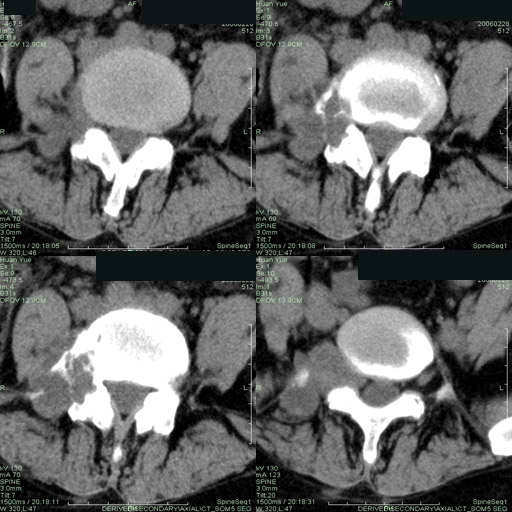

以下是引用听蝉观竹在2006-3-5 23:09:00的发言:[br]这个病例不考虑神经源性肿瘤,首先考虑转移瘤,因为它不是受压造成骨质吸收,而是从骨骼的松质部分由中心向外破坏的,不仅仅是横突,而且同侧椎弓根也破坏了。[br]神经源性肿瘤-----受压造成骨质吸收。[br]转移性肿瘤------从骨骼的松质部分由中心向外溶骨破坏,多见椎弓根也破坏。

以下是引用徐大夫在2006-3-5 20:32:00的发言:[br]骨缺损区边缘有硬化,结合部位,考虑神经源性良性肿瘤。